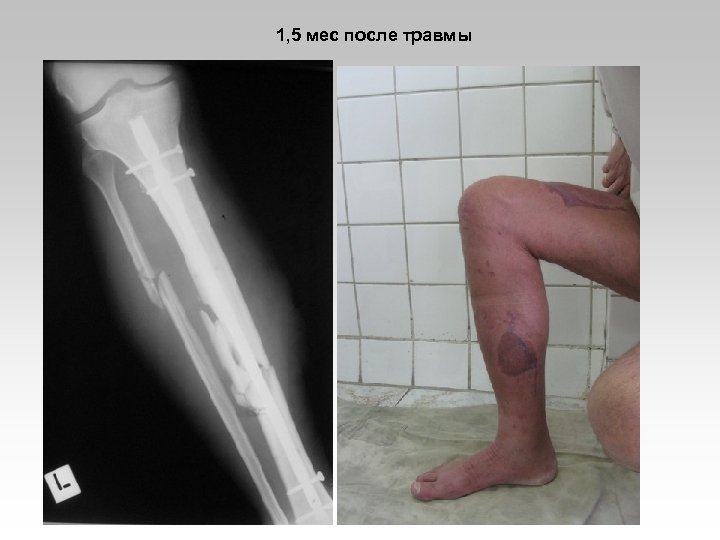

Пациент Г. , 49 лет. Сочетанная травма головы и конечностей. Открытый перелом большеберцовой кости III типа.

1, 5 мес после травмы